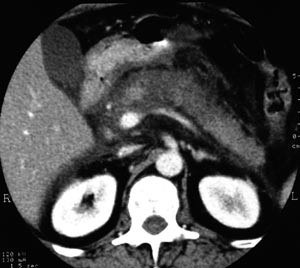

I tillegg til teksten er studiane vurdert systematisk i e-tabell 2 (5, 7) – (10, 12). Det vanlege inklusjonskriteriet i studiane er CT-påviste nekrosar i pancreas (fig 1 – 4) saman med klinisk akutt pankreatitt.